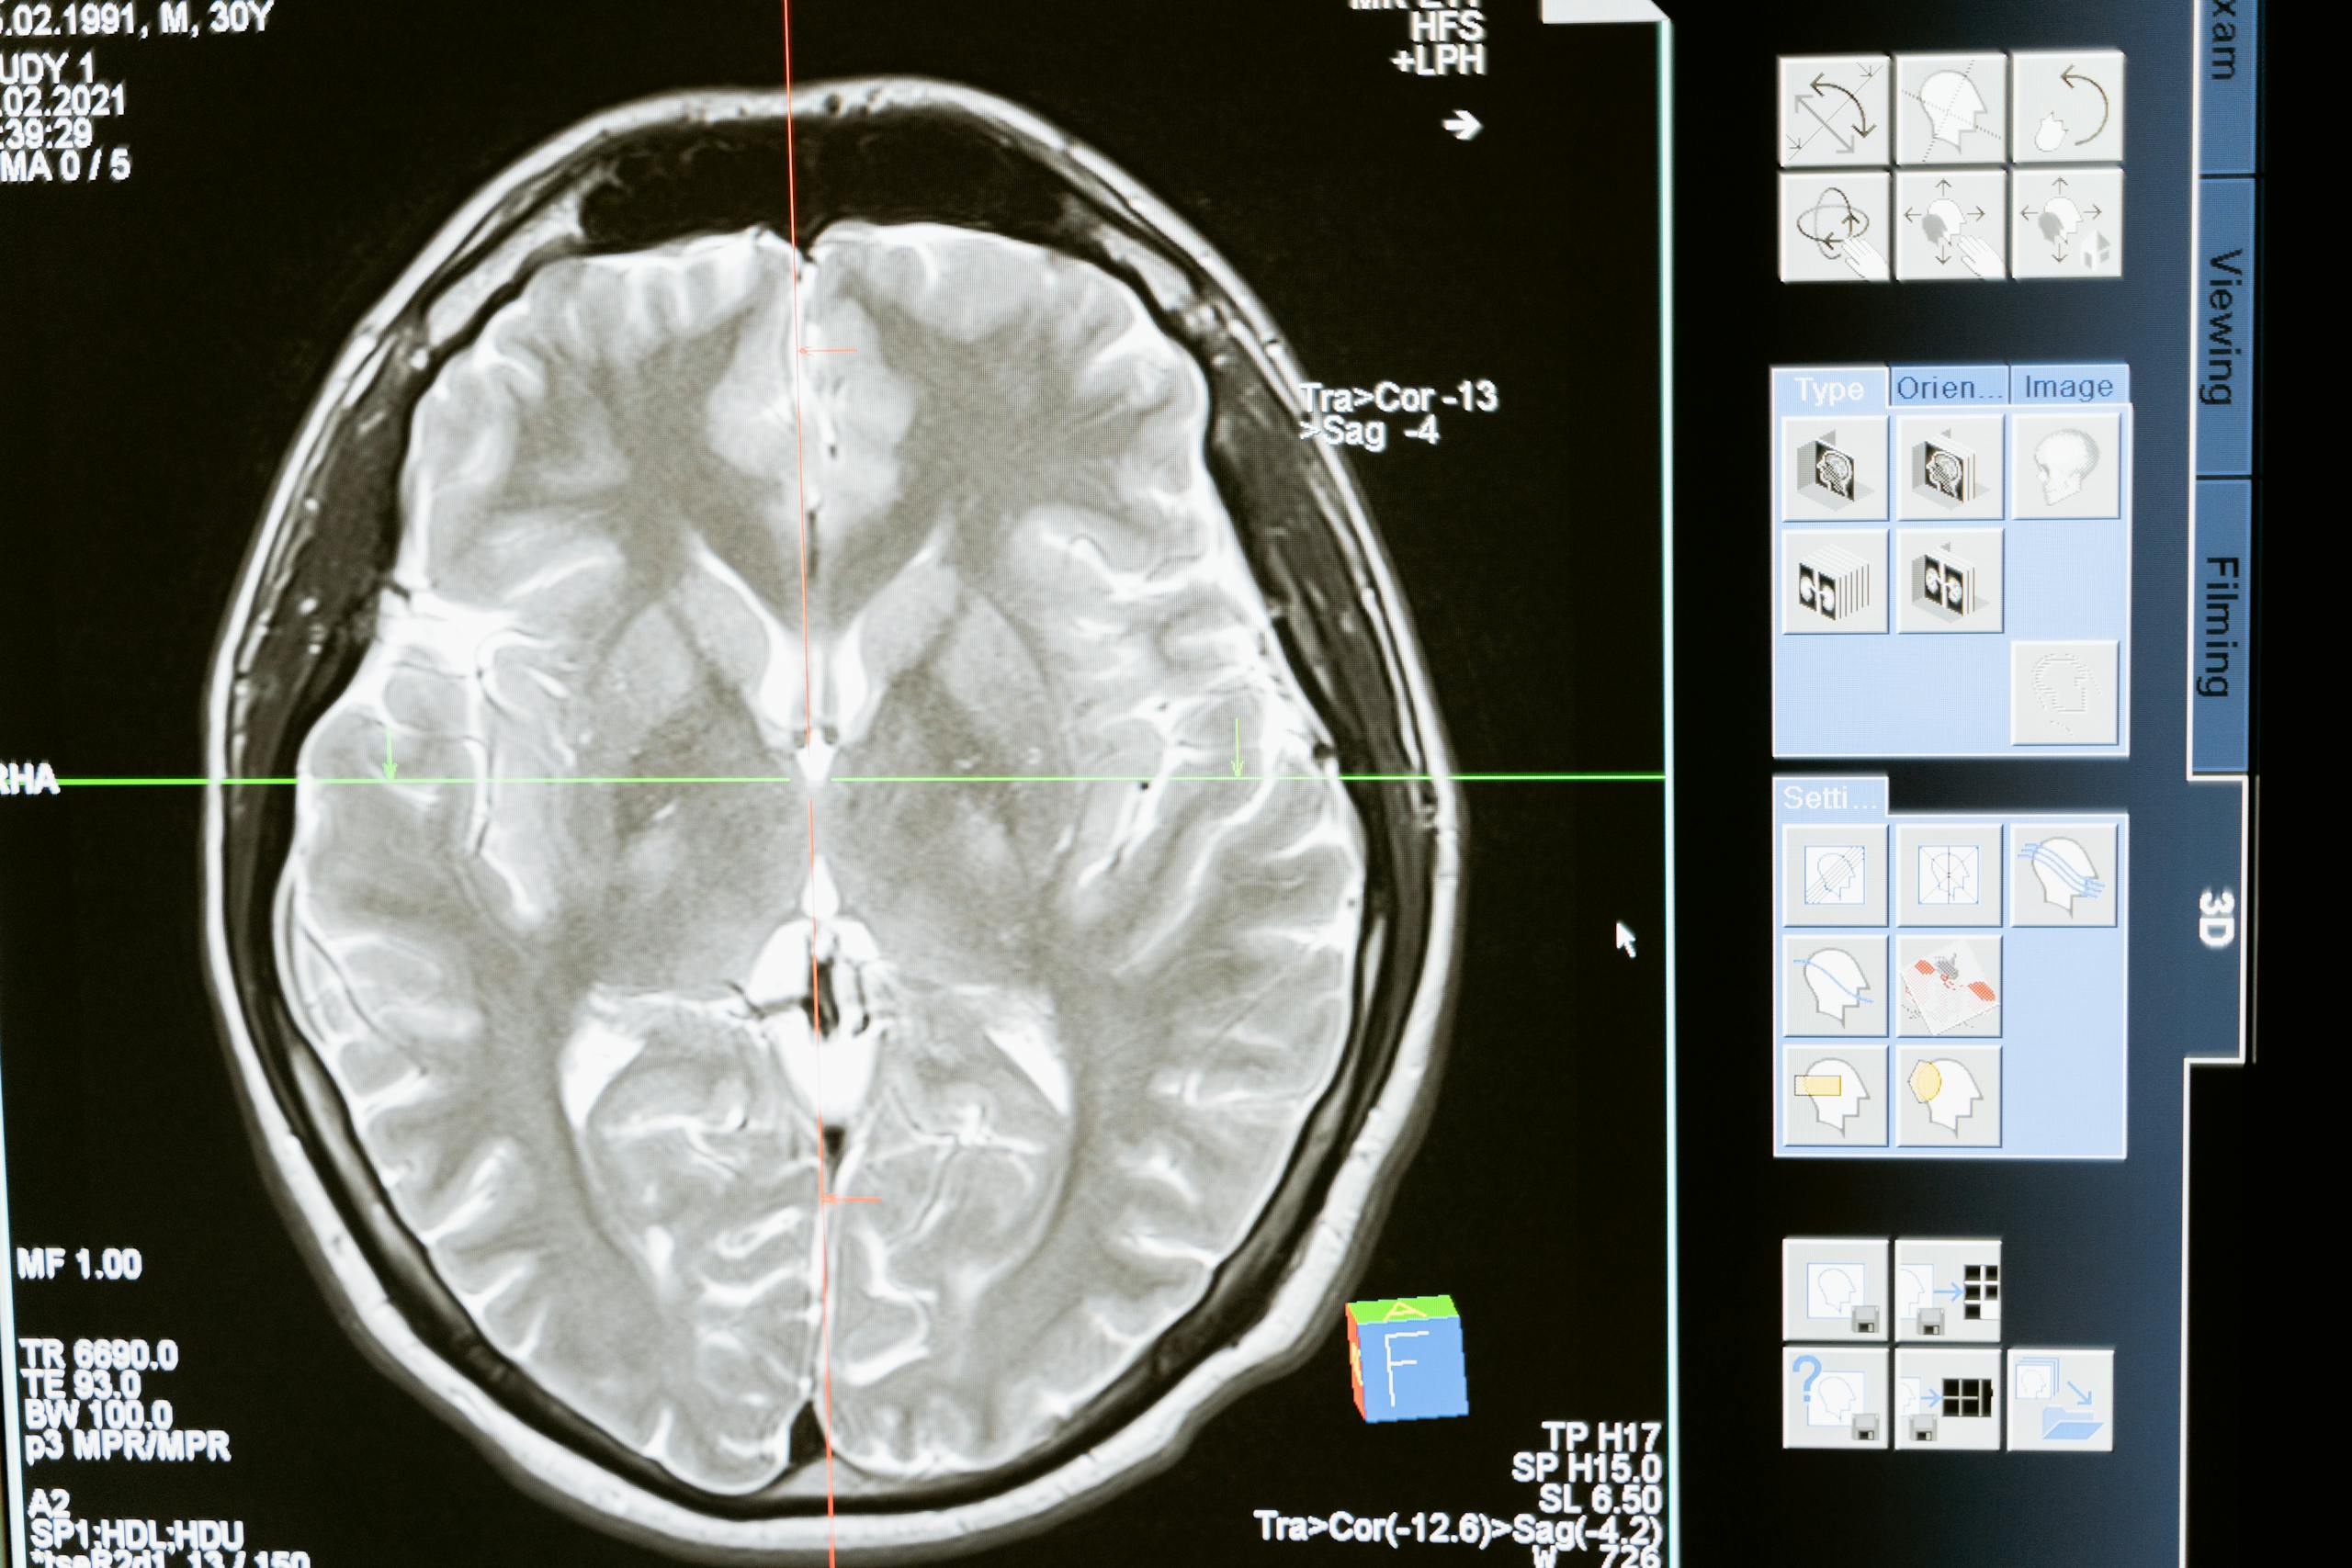

Extra Insight: What Is the Striatum?

The striatum is part of the basal ganglia, a group of structures deep in the brain that are essential for coordinating movement, learning habits, and even certain cognitive functions. It integrates signals from the cortex and sends them to other brain regions to help plan and execute movements.

The balance between these two systems is crucial. Disruption in striatal function is a major hallmark of Parkinson’s disease and Huntington’s disease.